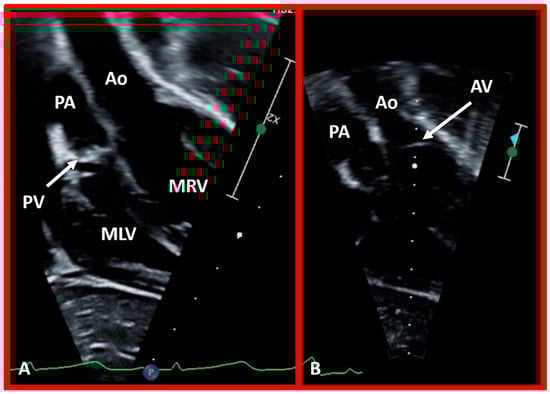

Based on the loop rule, the aortic valve to the right side of the pulmonary valve indicates a d-loop, and d-loop predicts that the RV is located on the right side and the LV on the left side. Similarly, the aortic valve positioned to the left of the pulmonary valve suggests an l-loop, which suggests that the morphologic RV is on the left while the morphologic LV is on the right (inverted) [3,4,5,10,23,37,38]. All the features described above can be defined by both echocardiography and selective cine angiography and are helpful in evaluating the looping status. Examples of d-loop in subjects with normally related great vessels (Figure 31), those with d-transposition of the great vessels (Figure 35) and those with dextrocardia (Figure 36), and those with l-loop illustrating inverted ventricles (Figure 40 and Figure 41) are shown.

Figure 40. Echo images in apical four-chamber projections of a child with ventricular inversion. The aortic valve (AV) and aorta (Ao) are located to the left of the pulmonary valve (PV) and pulmonary artery (PA), indicating an l-loop, and that morphologic right ventricle (MRV) is on the left, and the morphologic left ventricle (MLV) is on the right. In (A), the PV (arrow in (A)) is clearly seen, while AV is imaged in (B) (arrow in (B)).